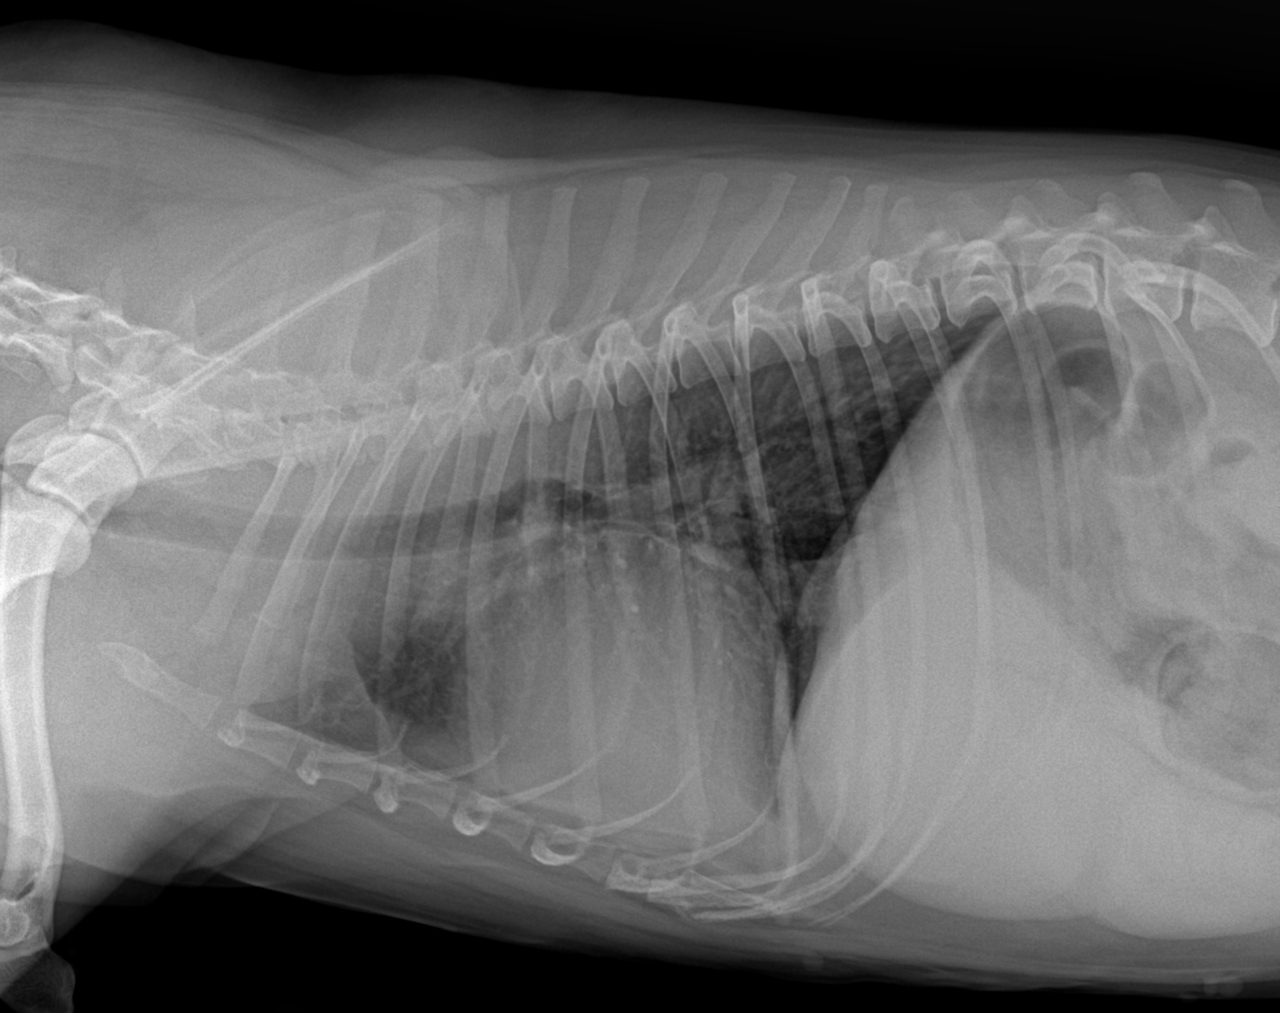

9歳の柴犬が散歩中に突然倒れる事があるとのことでかかりつけを受診しました。幼少時よりてんかん発作を発症する事があるが、今回の様子はてんかんの時とは異なる様だとのことで精査を希望され来院しました。心音は微弱でマッフルを呈していました。また、腹水の貯留も確認されました。心臓超音波検査では心膜液の貯留が確認されました。心嚢水の除去を行なったところ、出血性の心嚢水でした。数日間は心嚢水の除去のみで一般状態は改善していました。しかし、再発すると虚脱するといった症状が確認されたため、再発性の心タンポナーゼを回避するために、胸腔鏡下で心膜切除術を実施しました。同時に中皮腫、血管肉腫、特発性との鑑別にCTによる精査も実施しております。心膜の病理検査では腫瘍性の変化はなく、著しく繊維化した心膜であり、特発性と診断されました。胸腔鏡下での手術であったため、数日間の入院で痛みも少なく良好に経過しています。